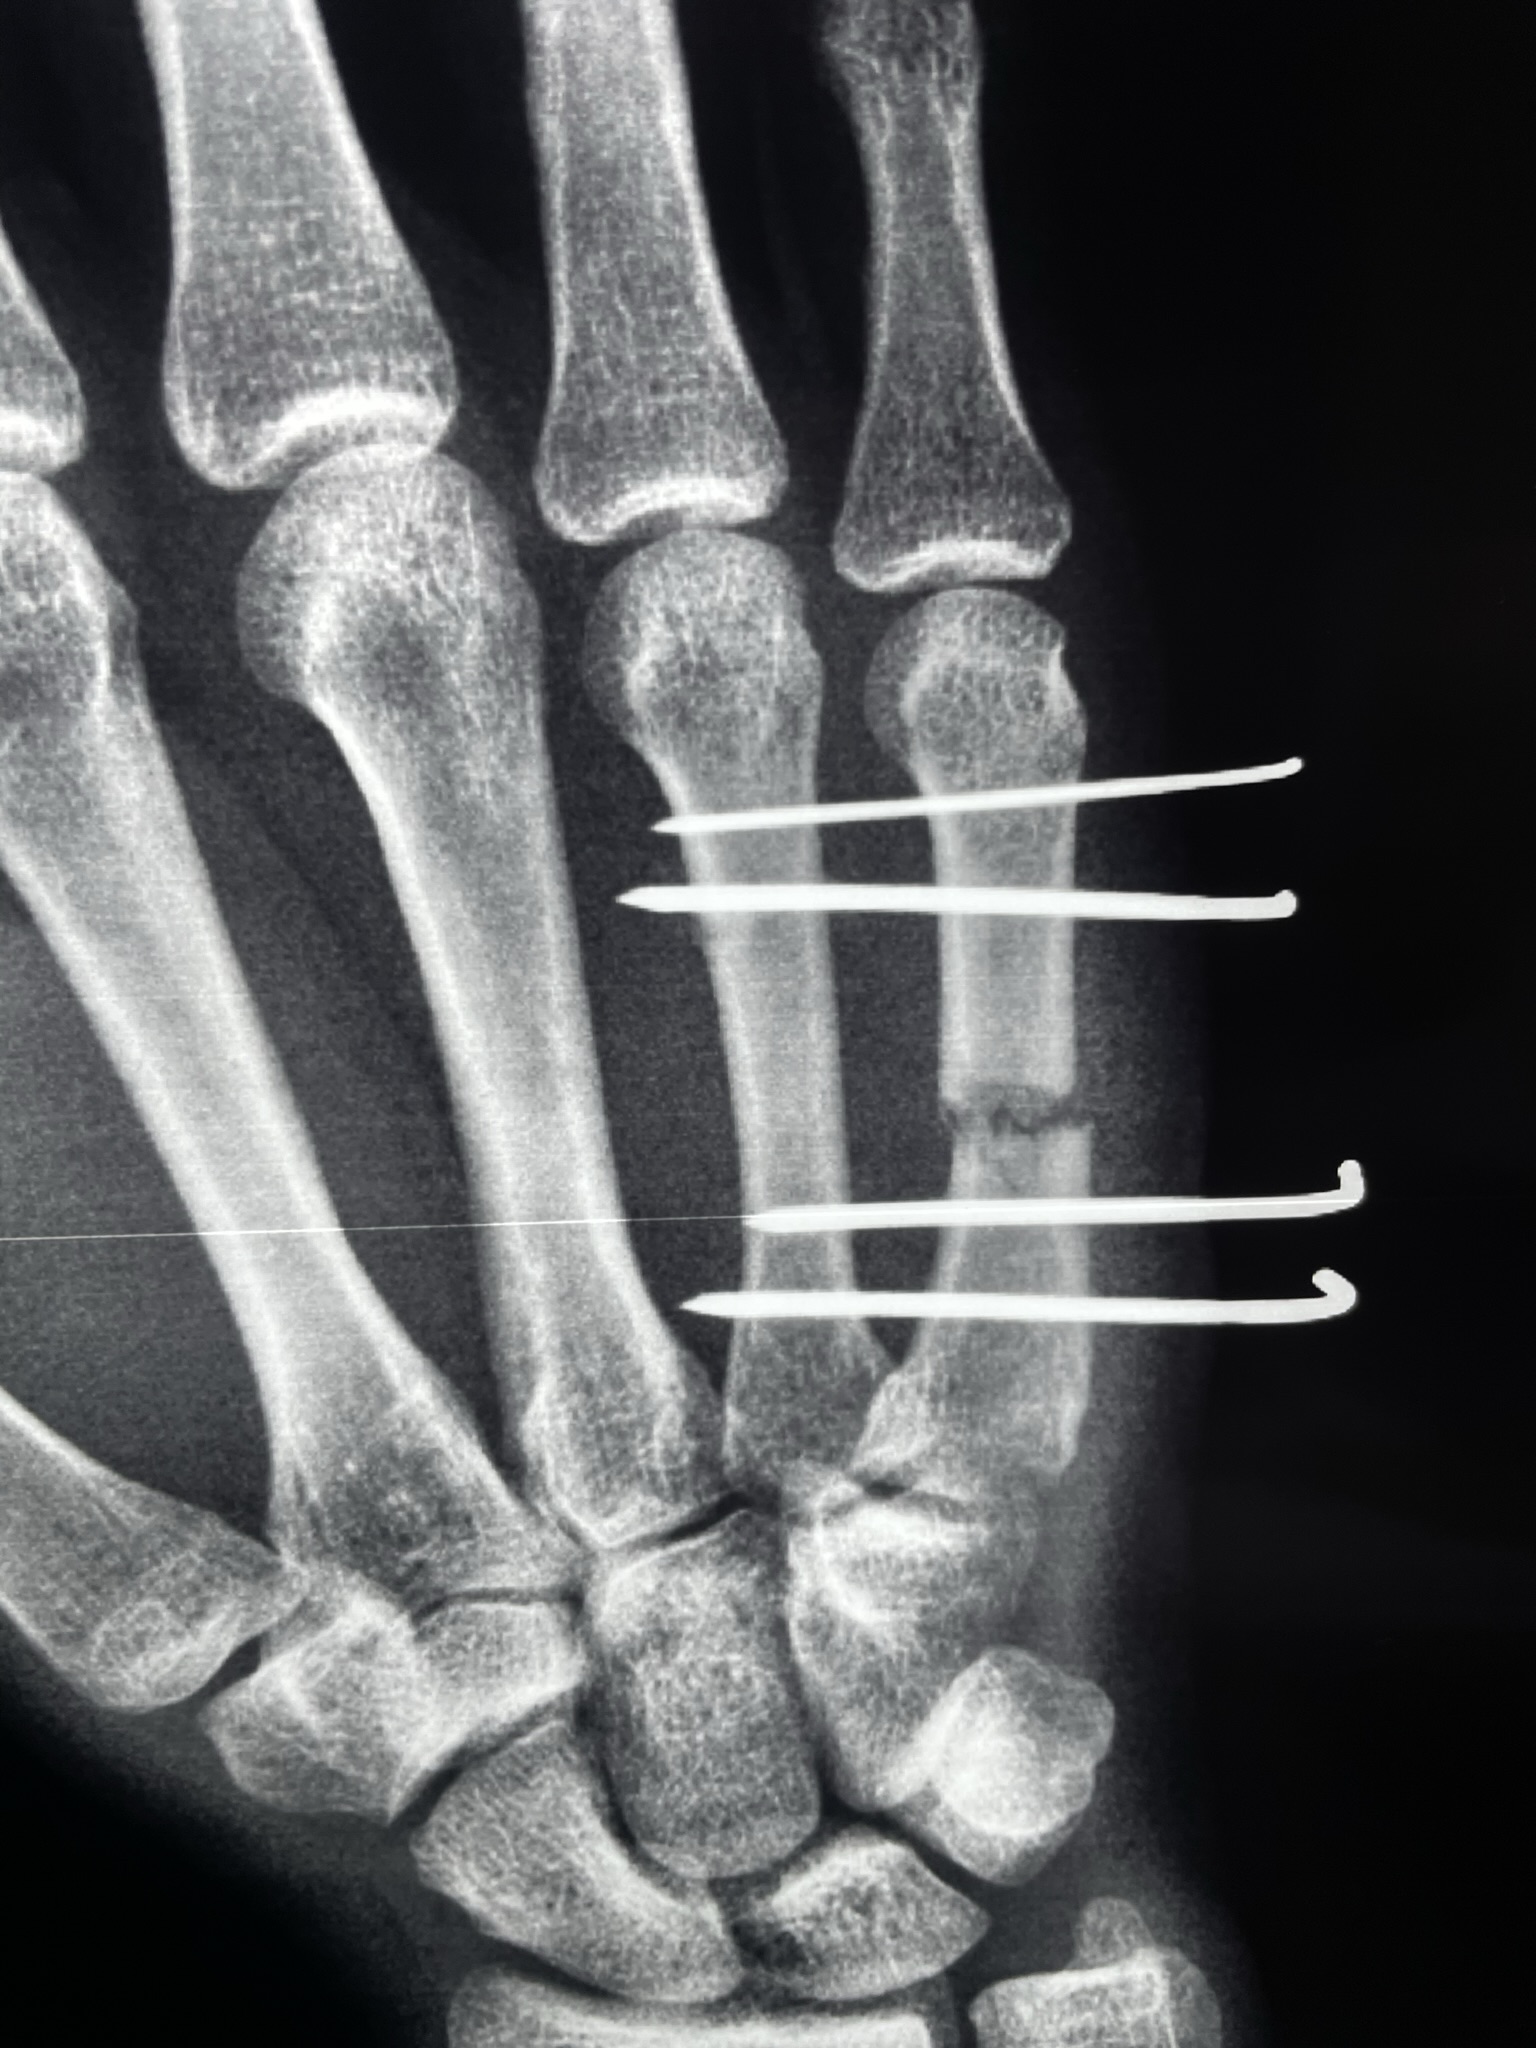

После операции

Проведена закрытая репозиция с фиксацией спицами. Отдельно задокументированы ранний послеоперационный период и восстановление функции.